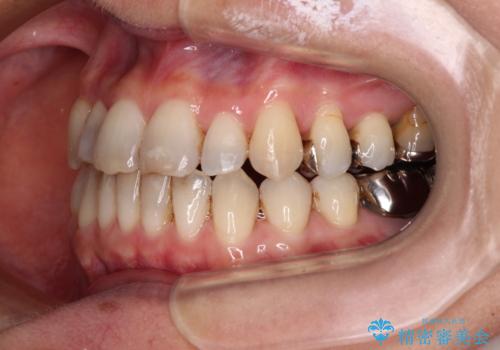

- 前歯の反対咬合を気にして来院された患者様です。

上顎骨の幅が下顎骨よりも小さいので、拡大装置により骨幅を広げて上下関係を改善すると同時にワイヤー矯正で反対咬合の改善を図り、その後インビザラインにて歯並びを整えることとしました。

上顎前歯の矮小歯は矯正治療の途中でオールセラミッククラウンを装着し、左右のバランスを整えることとしました。

急速拡大装置の使用により奥歯の咬み合わせが劇的に変わり、その変化を利用して反対咬合を改善することができました。

治療期間中は奥歯が咬み合わず、食事が取りにくいなどの不都合がありましたが、最終的にはきれいに整えることができました。